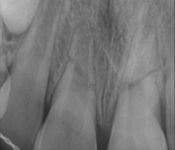

Pictured: Root Fractures/Splinting of Teeth and 1 Year Recall with Complete Root Formation

Parent of our 7-year-old patient was distraught by an injury that indicated horizontal root fractures in tooth #8 and tooth #9. Treatment involved splinting of teeth. After 1 year recall , the patient successfully had complete root formation.